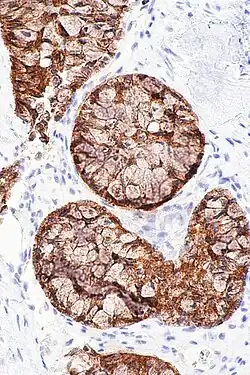

Screening for ALK positive lung cancer is now a standard of care and strongly recommended by the American Society of Clinical Oncology[7] as well as the European Society of Medical Oncology.[8] Screening in the United States of most often done with immunohistochemistry (IHC) staining or FISH.[7]